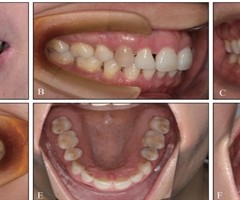

无托槽隐形矫治上颌扩弓效率的影响因素

[摘要]目的探究无托槽隐形矫治(CAT)过程中上颌扩弓效率的影响因素。方法筛选54名上颌扩弓矫治的非拔牙CAT患者,收集其基线数据,通过锥形束计算机断层扫描(CBCT)测量其牙冠和牙根长度,模型重叠测量其上颌扩弓效率和转矩变化,通过线性分析...